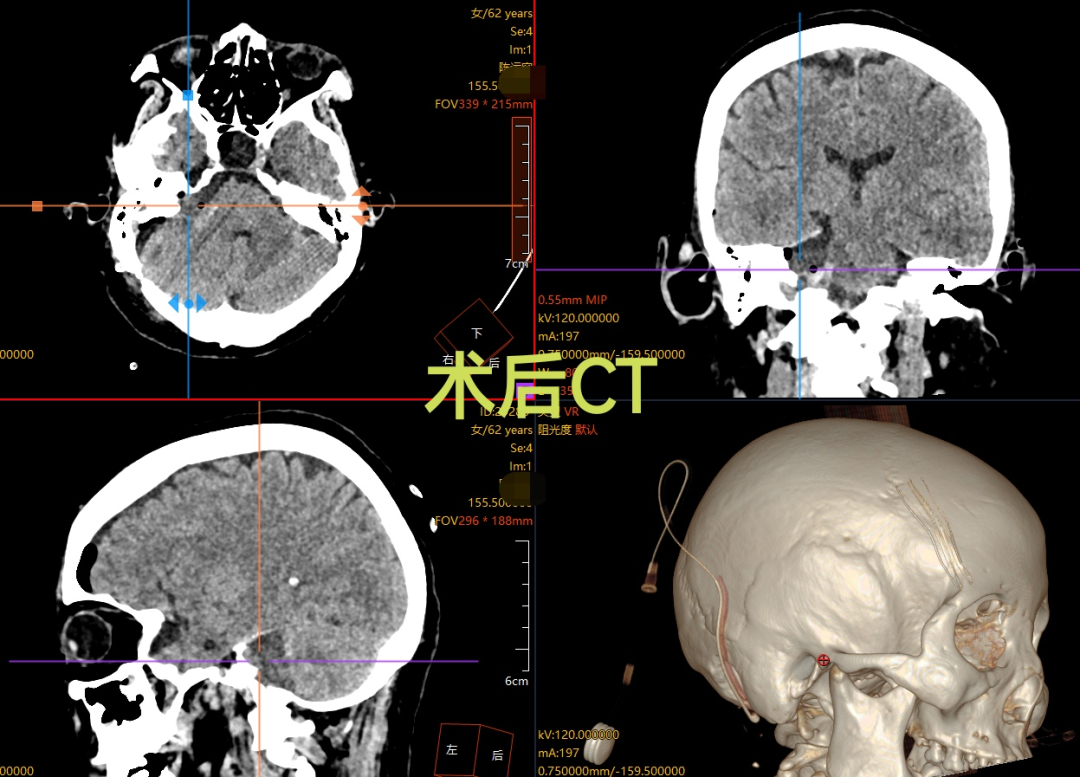

面对这一复杂病例,我院神经外科蔡璞主任团队迅速组建专项诊疗小组,制定了周密的手术方案。为最大限度降低创伤、提升精准度,手术摒弃了传统开放式大切口模式,采用机器人导航辅助技术。该系统如同为手术医生配备了“高清透视眼”与“实时GPS”,能在术中动态、精准定位肿瘤边界及周边血管、神经的细微结构,为手术操作划定“安全区”;同时,术中全程启用神经电生理监测系统,像“忠诚哨兵”般实时监护面神经与听神经功能——一旦手术器械接近神经组织,监测系统便会立即发出警报,引导医生及时调整操作路径。在蔡璞主任的带领下,医护团队密切配合、精准操作,最终顺利将肿瘤完整切除。术后检查显示,陈女士的面神经功能完好,残余听力也得到有效保留,目前恢复状况良好。